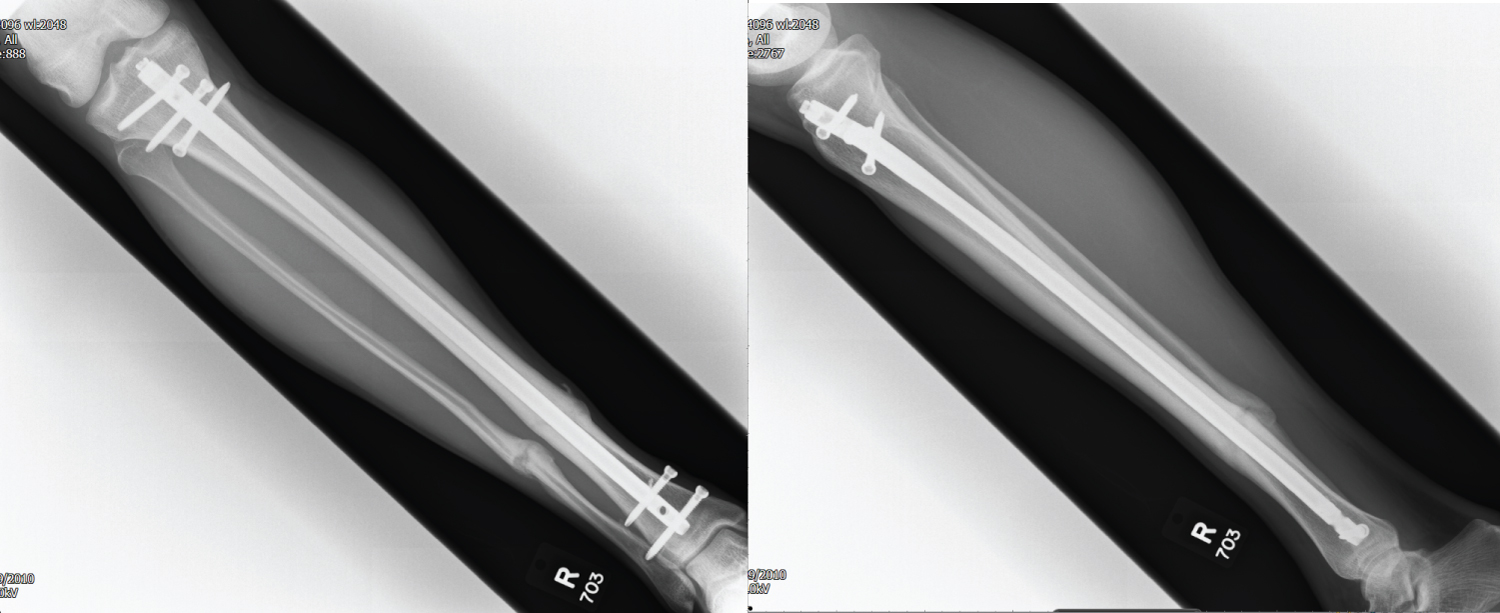

1 year post-operatively the prominence of the distal locking bolts caused pain when kicking a football and he was duly listed for removal of the distal bolts only 12 months post-operatively (Figure 3). Following recovery from bolt removal, a gradual return to football was allowed. Over the subsequent 12 years the patient suffering an insidious onset progression of pain in the distal tibial, particularly in the morning and whilst playing sport, prompting referral through to the orthopaedic services for follow-up 13 years post-operatively.

Figure 3: AP + Lateral X-ray 9 months post ORIF prior to distal screw removal. View Figure 3